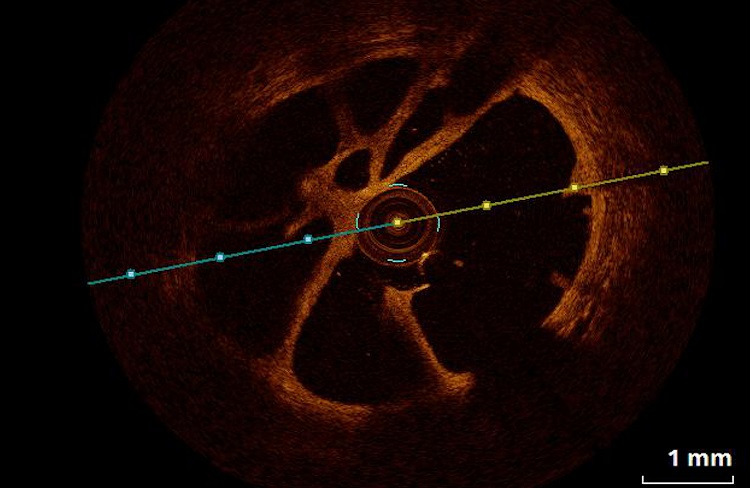

- cyfrowy system do obrazowania wewnątrzwieńcowego IVUS Volcano Philips;

- systemy do oceny czynnościowej zwężeń w tętnicach wieńcowych i płucnych – FFR/iFR Volcano Philips, Acist RXi Bracco Iamging, Quantien Abott ) do zabiegów kardiologicznych oraz angiologicznych;

- diagnostykę zmian granicznych stwierdzonych w trakcie koronarografii (zwężenia 40-70%), przy pomocy oceny czynnościowej zwężeń (FFR) oraz oceny morfologicznej (ultrasonografii wewnątrzwieńcowej -IVUS);

- Roik M, Wretowski D, Labyk A, Kostrubiec M, Irzyk K, Dzikowska-Diduch O, Lichodziejewska B, Ciurzynski M, Kurnicka K, Golebiowski M and Pruszczyk P. Refined balloon pulmonary angioplasty driven by combined assessment of intra-arterial anatomy and physiology–Multimodal approach to treated lesions in patients with non-operable distal chronic thromboembolic pulmonary hypertension–Technique, safety and efficacy of 50 consecutive angioplasties. Int J Cardiol. 2016;203:228-35.

- Rzadkim odległym powikłaniem ostrej zatorowości płucnej jest nadciśnienie płucne o etologii zakrzepowo zatorowej (chronic thromboembolic pulmonary hypertension, CTEPH). W Klinice prowadzimy pełną diagnostykę chorych z podejrzeniem CTEPH, a tod 2014 wykonujemy plastyki balonowe tętnic płucnych u chorych z potwierdzonym CTEPH nie zakwalifikowanych do leczenia kardiochirurgicznego. Zabiegi wykonywane są z zastosowaniem nowoczesnych metod wewnątrznaczyniowego obrazowania (FFR/IVUS/OCT) co zwiększa bezpieczeństwo i skuteczność tych zabiegów.

- Plastyki balonowe tętnic płucnych u chorych z potwierdzonym zakrzepowo zatorowym nadciśnieniem płucnym z zastosowaniem nowoczesnych metod wewnątrznaczyniowego obrazowania (FFR/IVUS/OCT), co zwiększa bezpieczeństwo i skuteczność tych zabiegów.